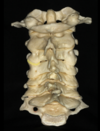

Atlas

Axis